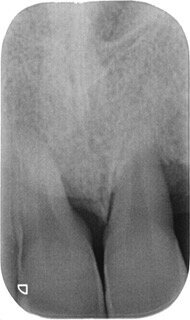

Una volta intercettata la patologia parodontale l’operatore ha il dovere di approfondire la diagnosi compilando una cartella parodontale completa e rilevando, a seconda della distribuzione dei sondaggi, radiografie intraorali periapicali per poter valutare l’espressione della patologia a carico dei tessuti profondi; infine l’attenta anamnesi familiare e individuale permette all’odontoiatra di inquadrare i molteplici fattori di rischio eventualmente correlati (fumo, diabete familiarità, età, stress etc.).

- L’operatore in grado di eseguire le cosiddette terapie correttive parodontali e implantari (terapia chirurgica rigenerativa, resettiva, conservativa, di sostituzione implantoprotesica) deve eseguirle se necessarie, inquadrando l’esecuzione al singolo caso parodontale sulla base di una attenta interpretazione del dato clinico – radiografico e di compliance del soggetto in esame (PD maggiore 6- 7mm, difetti intraossei, necessità protesiche o riabilitative-estetiche).